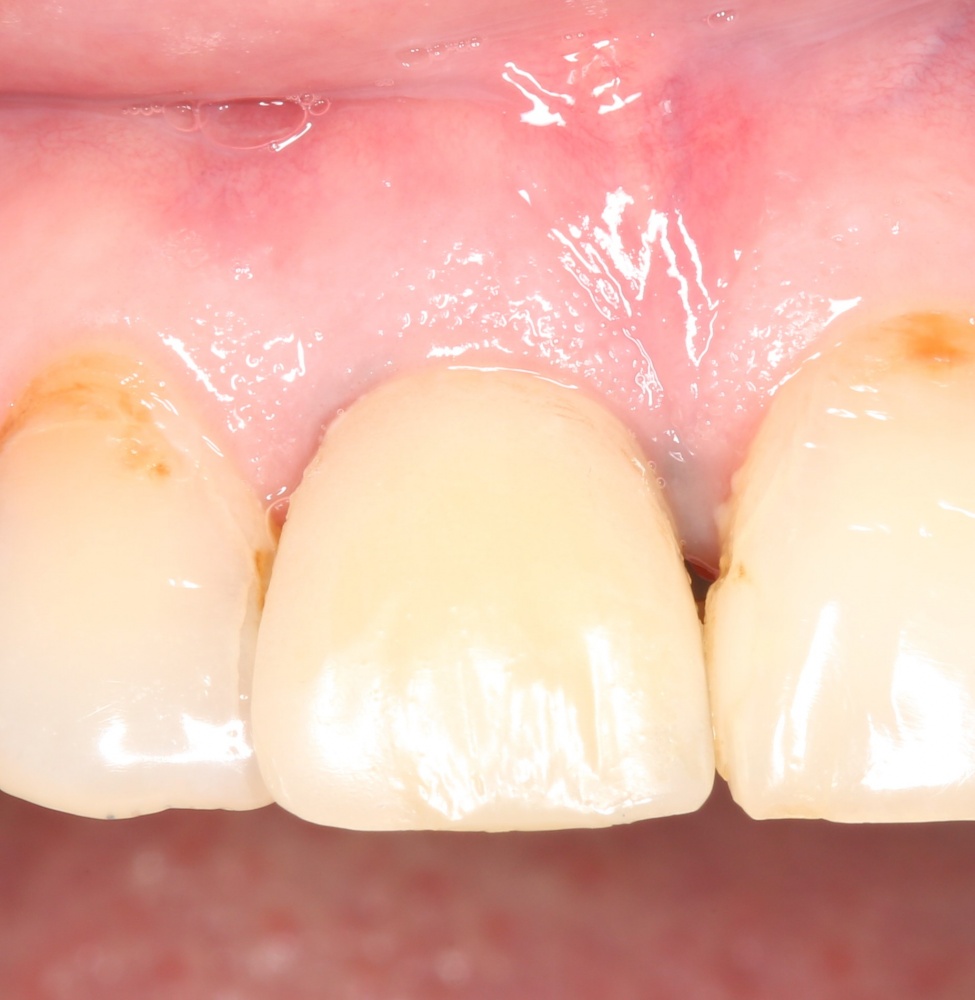

Недавно мой коллега Андрей Карнеев опубликовал в Facebook фотографию одной работы на финишных этапах протезирования:

Я горжусь тем, что тоже в ней поучаствовал.

Все началось с воспаления, свищевого хода и удаления зуба:

которая через три месяца, к моменту интеграции импланта, выглядит совсем иначе:

Ну и… к моменту установки постоянной коронки, у нас сохранился естественный контур прилегающей десны.

Что, собственно, нам и требовалось сделать.